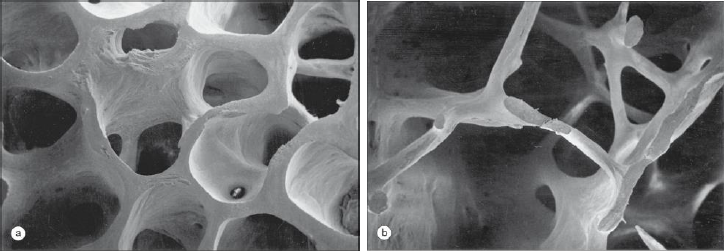

Au cours de l’ostéoporose post-ménopausique, des modifications osseuses vont survenir due à la privation oestrogénique, notamment lors du remodelage osseux, où la résorption osseuse est très active mais la formation osseuse peine à combler les cavités laissées par les ostéoclastes.

Cela conduit au fil du temps à accumuler une perte osseuse généralisée, avec un amincissement progressif voire des perforations des travées osseuses, qui vont compromettre sérieusement la solidité osseuse.